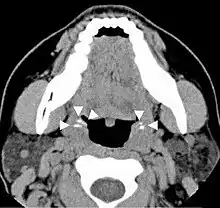

CT scan of tonsilloliths

Diagnosis is usually made upon inspection. Tonsilloliths are difficult to diagnose in the absence of clear manifestations, and often constitute casual findings of routine radiological studies. The cause of tonsil stones can include a multitude of sources from bacterial infections, streptococcus bacteria, viral infections, adenoviruses, influenza virus, enteroviruses and parainfluenza virus.[15]

Imaging diagnostic techniques can identify a radiopaque mass that may be mistaken for foreign bodies, displaced teeth or calcified blood vessels. CT scan may reveal nonspecific calcified images in the tonsillar zone. The differential diagnosis must be established with acute and chronic tonsillitis, tonsillar hypertrophy, peritonsillar abscesses, foreign bodies, phlebolites, ectopic bone or cartilage, lymph nodes, granulomatous lesions or calcification of the stylohyoid ligament in the context of Eagle syndrome (elongated styloid process).[18]